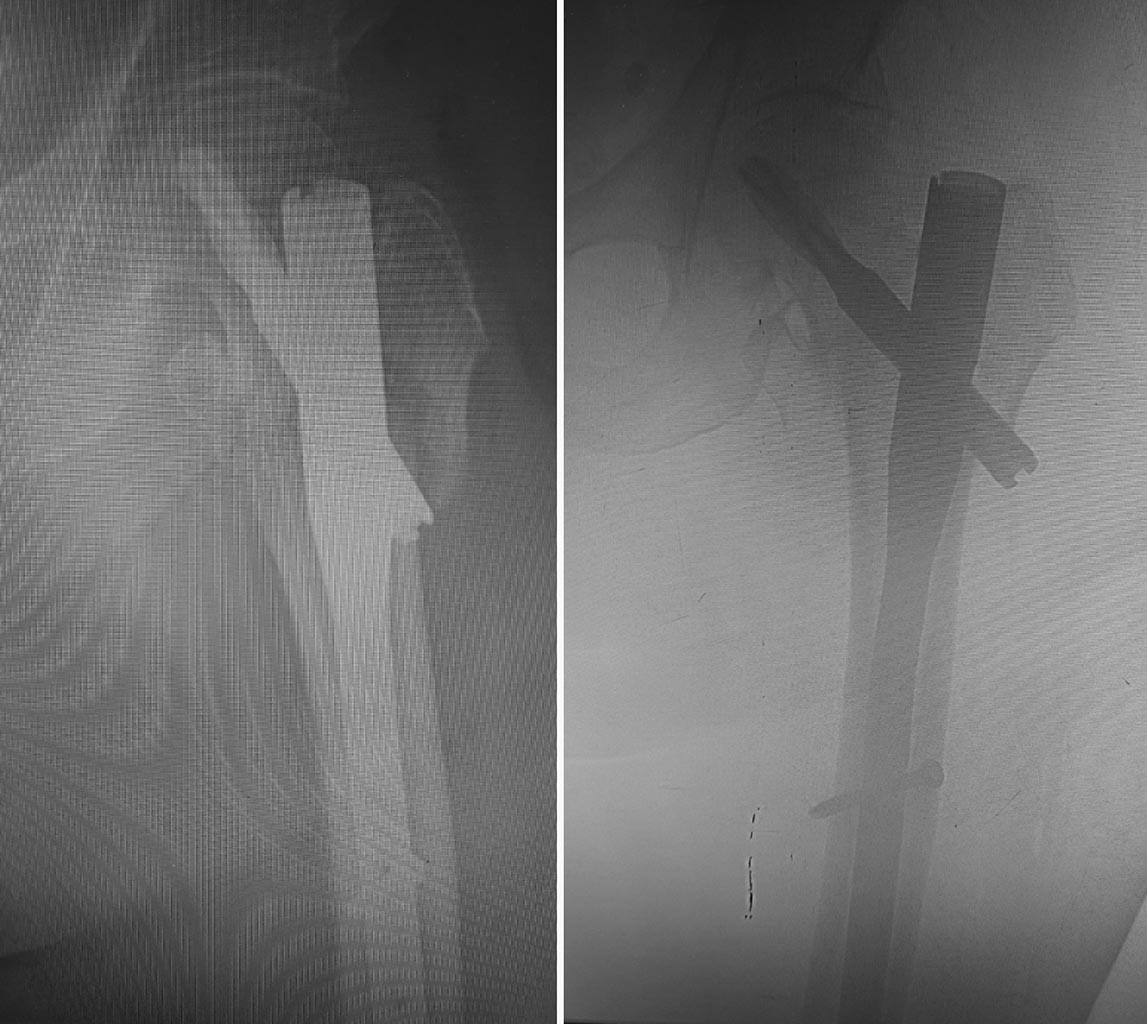

Использовали полер-спицы для форммрования канала и винт Шанца для

удержания отломка б.вертела при заведении гвоздя.